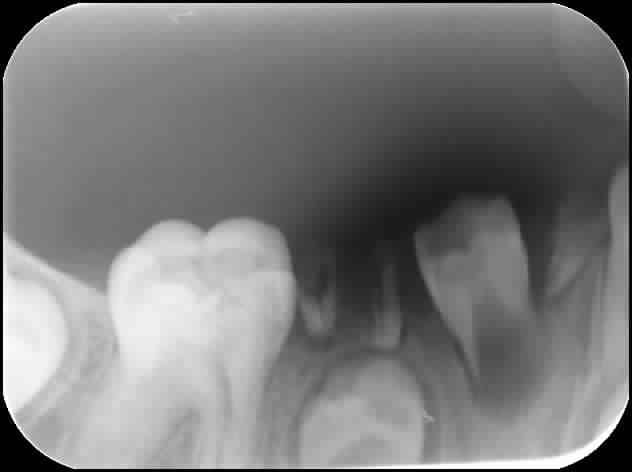

Je viens de voir à l'instant un jeune patient (7 ans) qui présente de multiples caries.

Rien que le secteur 4 est une catastrophe, et je ne parle pas du reste. Plusieurs dents définitives sont touchées plus ou moins gravement.

Bref, mon gros soucis c'est que faire de la dent 44 avec sa carie occlusale plus que profonde ? Vous verrez à la radio qu'elle est bien abimée...